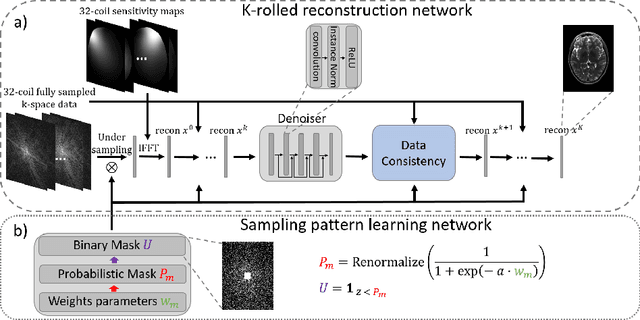

The previously established LOUPE (Learning-based Optimization of the Under-sampling Pattern) framework for optimizing the k-space sampling pattern in MRI was extended in three folds: firstly, fully sampled multi-coil k-space data from the scanner, rather than simulated k-space data from magnitude MR images in LOUPE, was retrospectively under-sampled to optimize the under-sampling pattern of in-vivo k-space data; secondly, binary stochastic k-space sampling, rather than approximate stochastic k-space sampling of LOUPE during training, was applied together with a straight-through (ST) estimator to estimate the gradient of the threshold operation in a neural network; thirdly, modified unrolled optimization network, rather than modified U-Net in LOUPE, was used as the reconstruction network in order to reconstruct multi-coil data properly and reduce the dependency on training data. Experimental results show that when dealing with the in-vivo k-space data, unrolled optimization network with binary under-sampling block and ST estimator had better reconstruction performance compared to the ones with either U-Net reconstruction network or approximate sampling pattern optimization network, and once trained, the learned optimal sampling pattern worked better than the hand-crafted variable density sampling pattern when deployed with other conventional reconstruction methods.